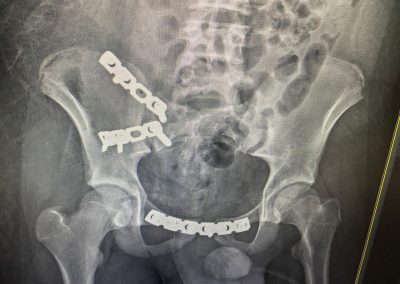

ياسين محمد أمين العمر:١٧ عامًا اصيب بكسر غير ثابت متفتت بالحوض يناير ٢٠٢٣